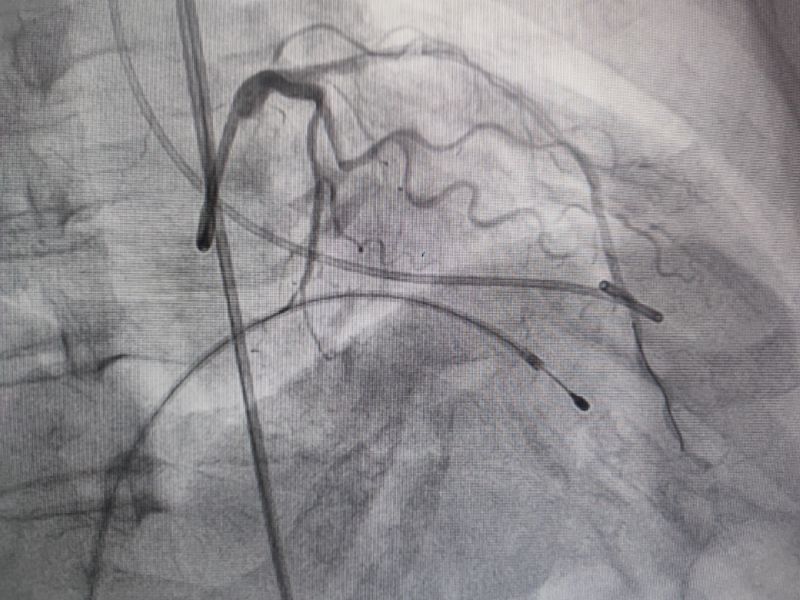

經(jīng)過(guò)多輪嚴(yán)謹(jǐn)?shù)男g(shù)前討論,在吳棟梁院長(zhǎng)的專業(yè)指導(dǎo)下,崔旭輝主任醫(yī)師團(tuán)隊(duì)決定在臨時(shí)起搏器的安全保護(hù)下,為患者實(shí)施冠狀動(dòng)脈造影術(shù)及室間隔化學(xué)消融術(shù)。術(shù)中,團(tuán)隊(duì)通過(guò)造影精準(zhǔn)鎖定第一穿隔支為消融靶血管。測(cè)壓數(shù)據(jù)顯示:左室壓260/15mmHg,流出道173/6mmHg,主動(dòng)脈壓106/70 mmHg,壓力階差達(dá)87mmHg。隨后,團(tuán)隊(duì)使用2.0X15mm預(yù)擴(kuò)球囊以8atm壓力阻斷第一穿隔支遠(yuǎn)端血流1分鐘,再次測(cè)壓時(shí),壓力從269/7mmHg驟降至174/4mmHg,這一結(jié)果充分證實(shí)該血管正是室間隔的有效供血血管。緊接著,團(tuán)隊(duì)通過(guò)SPRINTER OTW2.0×8mm球囊緩慢注入1.4ml無(wú)水酒精。10分鐘后復(fù)測(cè),左心室壓降至136/5 mmHg,主動(dòng)脈壓為112/93 mmHg。術(shù)后第2天,王女士胸悶、氣短、心悸等不適癥狀完全消失。復(fù)查心臟彩超顯示:EF值與FS值保持穩(wěn)定,收縮期左室流出道血流速度降至252cm/s,PG值為25mmHg。

消融后造影

測(cè)壓

消融時(shí)測(cè)壓